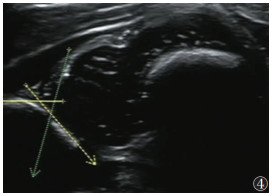

2.220例CMT合并DDH中,左侧DDH 8例,右侧DDH 6例,双侧DDH 6例。20例40髋中,Ⅰ型14髋(35.0%)(图 1)、Ⅱa型17髋(42.5%)(图 2)、Ⅱb型5髋(12.5%)(图 3)、Ⅱc型1髋(2.5%)(图 4)、Ⅲ型2髋(5.0%)(图 5)、Ⅳ型1髋(2.5%)(图 6)。

| 图 4 女,20 d,左髋α=49°,β=75°,GrafⅡc型,骨顶缘扁平,软骨顶仍覆盖股骨头 |

目前,超声已被认为是诊断CMT和DDH最敏感的工具之一,并被广泛用于两者的诊断[2, 13]。一方面,超声可用于量化CMT患儿肌肉纤维化程度,确定肿块的大小和位置,并指导临床制订治疗方案[17]。本组非肿块型98例,肿块型78例。非肿块型常仅表现为头歪向一侧,此时运用超声测量双侧的SCM的厚度、对比是否有局限性增厚,观察肌纤维排列、肌纹理回声及与周围组织关系从而早期诊断CMT;对于肿块型,超声可明确肿块来源,排除淋巴管瘤、淋巴结等其他颈部肿块。根据患侧SCM的声像图特点推测肌肉纤维化程度,从而选择治疗措施,并通过超声计算出SCM挛缩长度、确定临床手术方案和松解范围[1, 18-21]。此外,超声在后期疗效观察和判断预后上也有重要价值,通过测量治疗前后SCM厚度、肿块大小,以及观察病变区血流情况,有利于评估CMT疗效。另一方面,相对于体格检查较明显的CMT,DDH可能更易忽视;尤其6个月以内的婴幼儿,因髋臼软骨未骨化X线不能显像,早期诊断DDH更困难。而超声波可穿透软骨,清晰显示关节囊、关节盂唇、股骨头软骨及髋臼等解剖结构;其中Graf超声静态测量方法因敏感性高,且观察者间的图像采集测量解读差异小、可重复性较高等优点,能更早期发现DDH,在婴儿髋关节超声检查中最普及[16, 22-23]。本组176例CMT患儿,通过Graf方法对髋关节进行分型,显示并发DDH 20例(40髋),其中Ⅰ型14髋(35.0%)、Ⅱa型17髋(42.5%)、Ⅱb型5髋(12.5%)、Ⅱc型1髋(2.5%)、Ⅲ型2髋(5.0%)、Ⅳ型1髋(2.5%),临床上根据具体病理阶段选择和实施合适的治疗,病情均得到不同程度的改善、获得满意的治疗效果。此外,应用彩色多普勒超声还可监测DDH治疗过程中股骨头血供情况,以减少股骨头坏死的发生[24]。